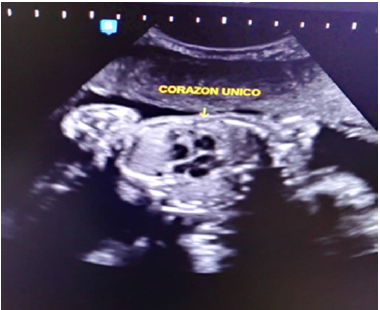

Es de vital importancia reconocer los hallazgos ecográficos que hacen sospechar el diagnostico de siameses destacándose: gestación gemelar monocorial monoamniotica, en el primer trimestre ver dos embriones y una sola vesícula vitelina, posicion fija de los gemelos que se mantiene a pesar de la movilización materna y repetición de la exploración ecográfica transcurrido un tiempo, visualización de las cabezas y los cuerpos fetales al mismo nivel, incapacidad de separar los cuerpos fetales, mayor número de vasos en el cordón umbilical, presencia de anomalías fetales sobre todo cardiacas, presencia de corazon único, inusual proximidad de las extremidades y extensión de las columnas vertebrales.(3).

Se trata de paciente femenina de 19 años, sin antecedentes familiares, personales y patológicos conocidos, IV gestas, II cesáreas, I aborto, FUR 18/08/2018, quien acude a especialista en medicina materno-fetal y en vista de hallazgos ecográficos es referida a la Unidad de Perinatología y Medicina Materno-Fetal del Hospital Materno Infantil Dr. José María Vargas, siendo evaluada el 13 de febrero de 2019, donde se realiza estudio ultrasonográfico Perinatal en tiempo real, con transductor convex de 3,5 mHz, ecógrafo marca Esaote, visualizándose estructuras fetales compatibles con dos fetos que correspondían a un embarazo múltiple doble, se identificaron ambos polos cefálicos ubicados en el mismo plano de corte durante la exploración (Figura 1), 4 extremidades superiores, tórax y abdomen de ambos fetos fusionados, corazon único (Figura 2), de difícil evaluacion, impresionando defecto septal ventricular de 4,6 mm (Figura 3), 2 cámaras gástricas (Figura 4), 2 vejigas, sexo femenino, 4 extremidades inferiores, una sola placenta anterior, grado I, grosor 42 mm, con índice de líquido amniótico (ILA) máximo bolsillo vertical (MBV) de 43 mm. Concluyéndose estudio ecográfico con diagnósticos de: Embarazo múltiple doble monocorial monoamniotico (Duplicata completa: siameses toracoonfalopago) de 25 semanas más 4 días por fecha de ultima menstruación con corazon único asociado a posible comunicación interventricular (CIV) sub-aortica.